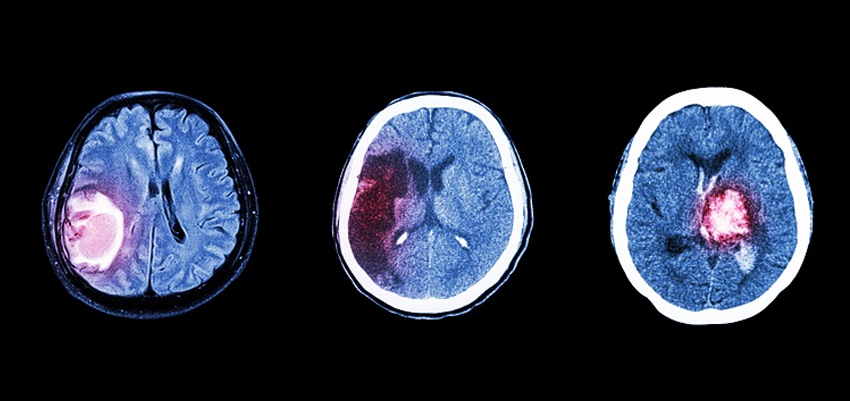

Surgery stands as one of the primary treatment modalities for brain cancer. Neurosurgeons, specializing in brain and nervous system surgery, work meticulously to remove as much of the tumor as possible. Advances in surgical techniques, such as image-guided surgery and neuro-navigation, have significantly improved precision, reducing the impact on surrounding healthy tissue.

Radiation therapy employs high-energy beams to target and destroy cancer cells. For brain cancer patients, specialized techniques like stereotactic radiosurgery and proton therapy offer precise and focused radiation delivery. These advancements maximize treatment efficacy while minimizing damage to adjacent healthy brain tissue.